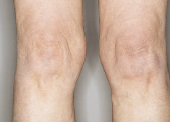

앞무릎 관절염 – 계단 오르기, 앉았다 일어날 때 유난히 아픈 이유

무릎이 아프긴 한데, 특히 앞쪽이 욱신거리거나 찌릿하게 아프고,

계단을 오르거나 쪼그려 앉을 때,

혹은 오래 앉았다 일어설 때 유독 무릎 앞부분이 ‘딱딱’ 소리 나며 뻐근하다면?

이런 증상은 흔히 말하는 '무릎 관절염'이 아닌

앞무릎(슬개대퇴) 관절염, 즉 슬개골 연골연화증 또는 슬개대퇴 통증 증후군일 가능성이 높습니다.